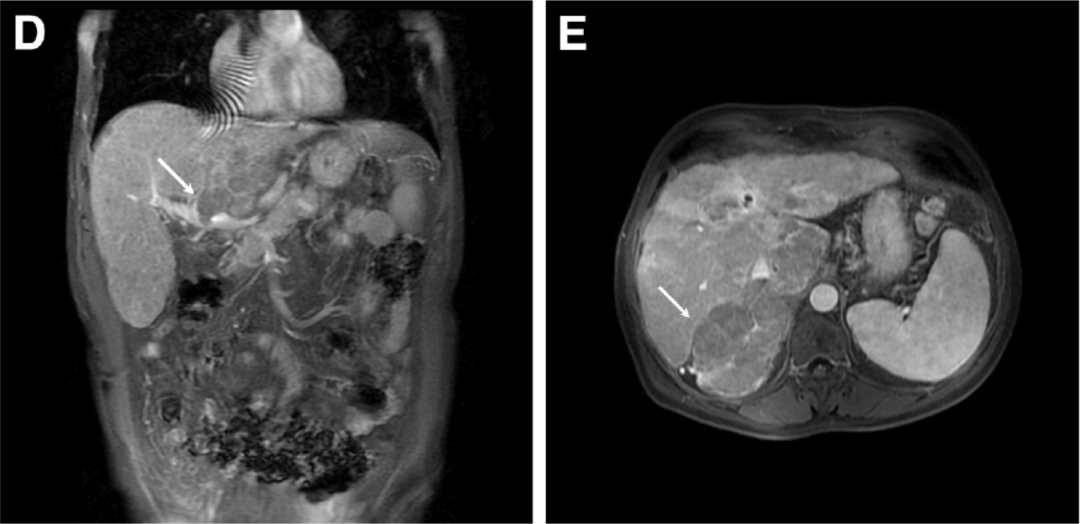

核磁共振成像显示肝内多发多血管结节(图B,箭头)伴假包膜(图C,箭头)、肿瘤门静脉血栓 (图D,箭头)和右侧肾上腺肿块(图E,箭头),符合转移性多灶性肝细胞癌的诊断。